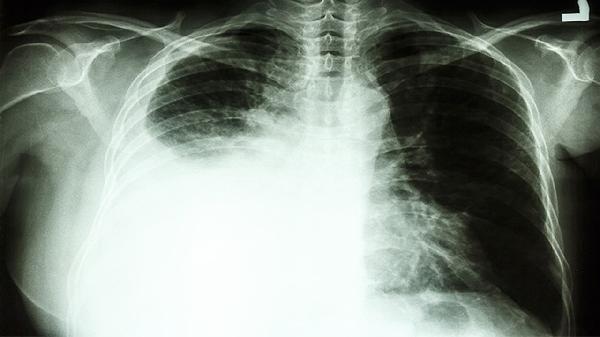

在胸部CT等影像学检查上,肺结节与肿瘤的特征有所不同。良性肺结节多表现为密度均匀、边缘光滑清晰、可有钙化(特别是层状、爆米花样钙化多见于良性)。恶性肺结节或肿瘤则常表现为密度不均匀(如磨玻璃密度、混合磨玻璃密度)、边缘不规则(有毛刺、分叶征)、胸膜牵拉、内部可见空泡征或支气管充气征。增强CT扫描时,恶性结节往往有较明显的强化。这些影像学特征是临床医生进行初步鉴别诊断的重要依据。